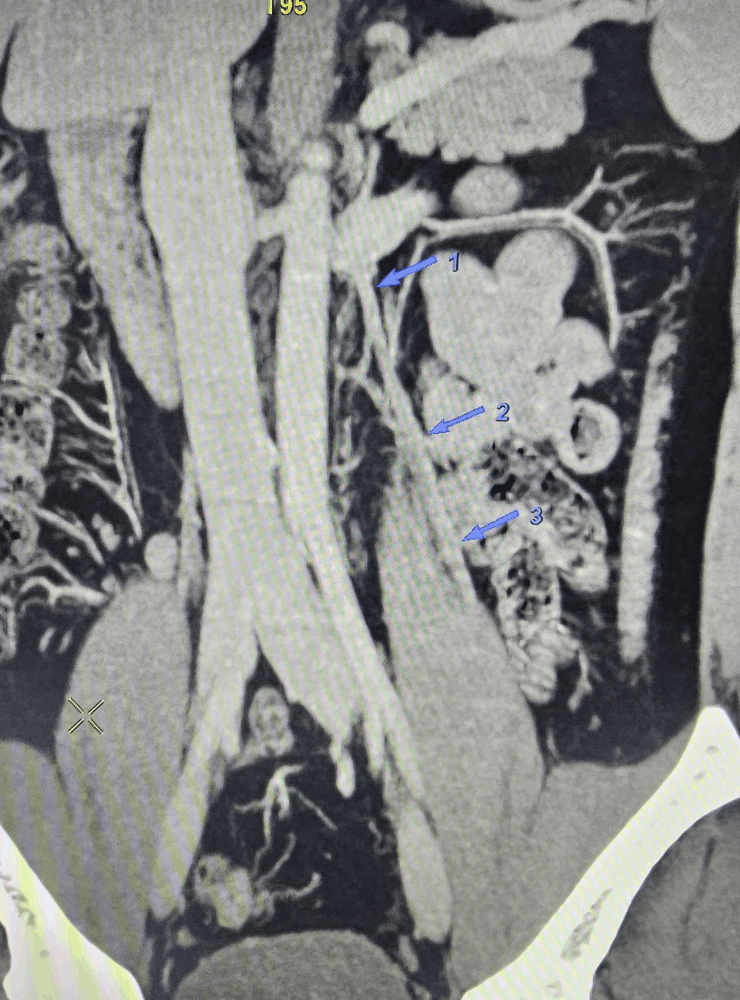

During embolization, the abnormal testicular veins are blocked from inside using coils and other embolic materials so that high‑pressure blood no longer flows through them. This helps decompress the varicocele and can improve symptoms such as scrotal heaviness, pain and fertility issues.

- Venogram to map abnormal testicular veins and confirm varicocele.

- Coil embolization and/or other embolic agents are used to block the refluxing veins.

- Completion check to ensure there is no further abnormal back‑flow to the scrotal veins.